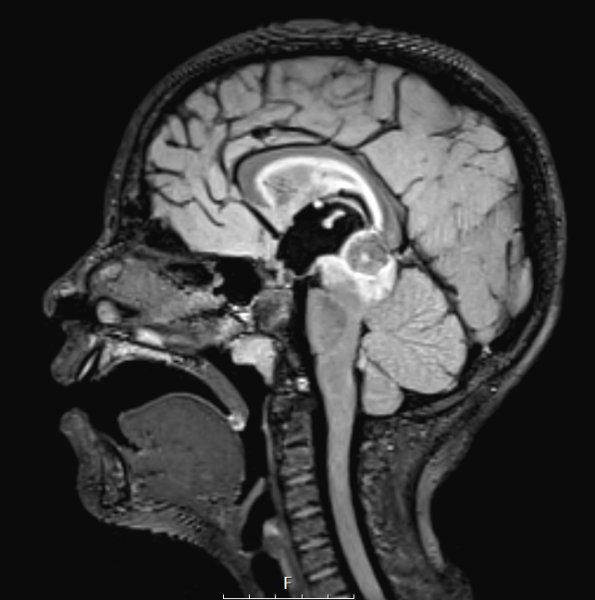

A T2-weighted scan shows a hyperintense rim around the pineal mass.